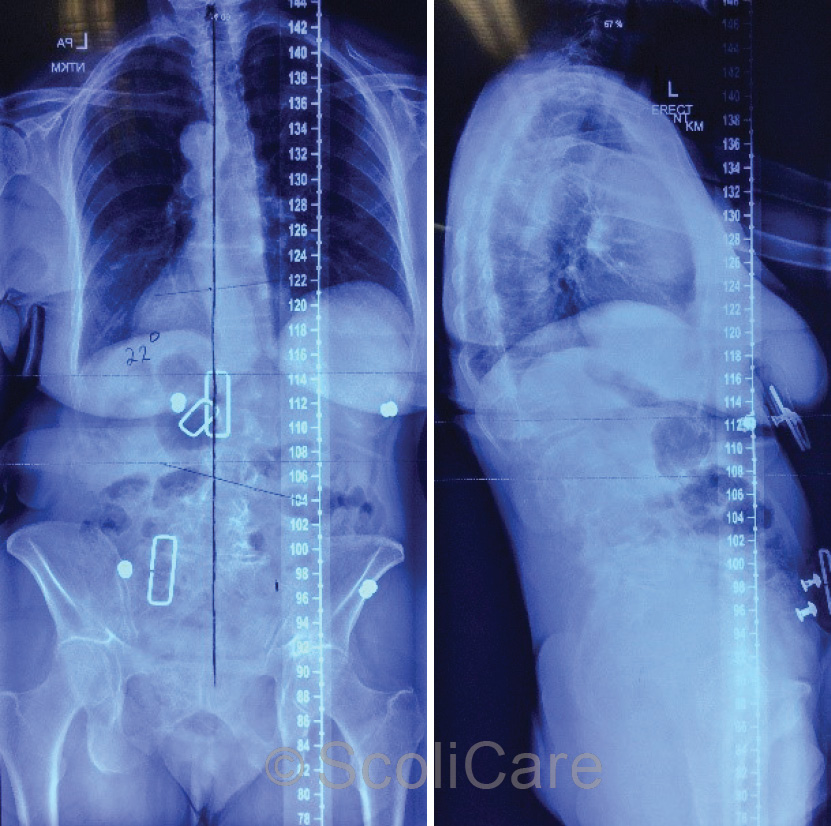

Plain films demonstrated that there was no significant change in the magnitude of the curve in-brace, however the patient’s coronal balance was significantly improved with the patient’s posture being more aligned with the central sacral vertical line through C7 and S2 (Figure 3).

Figure 4: Posteroanterior in-brace x-ray (Left),

Lateral in-brace x-ray (Right)